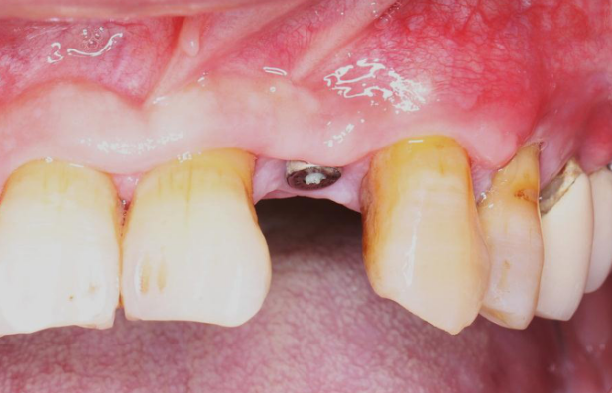

旋入种植体,初期稳定性为 30N。

直接上愈合基台。

缝合手术切口

瑞拜欧可吸收生物膜具有一定抗菌活性,复合PRF保护,尝试拔牙创开放愈合,保证了龈乳头原位缝合、避免了膜龈联合位置异位,有利于日后的美学效果,术后常规口腔护理、漱口、服用抗生素5天。